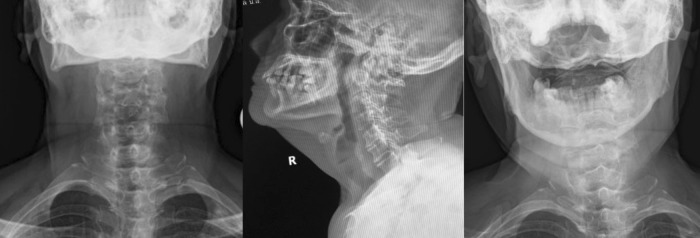

Fig. 1.

Plain radiographs of the cervical spine in anteroposterior (left panel), lateral (middle panel), and open mouth views (right panel) revealed generalized osteoarthritis of the cervical spine with os odontoideum and posterior atlantoaxial subluxation. No rotatory subluxation was seen